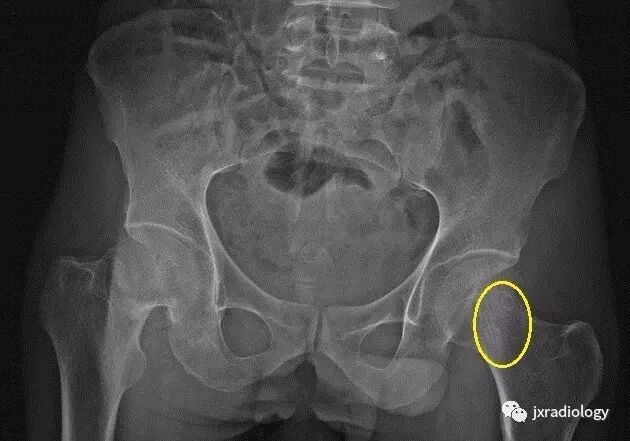

影像表现:X 线平片上表现为伴有清晰薄层硬化缘的环形(囊状)透亮区,CT 上表现为圆形 或类圆形的皮质下局灶性骨质缺损,周围见薄层硬化带环绕,边缘锐利,部分较大病灶在病灶层面或上下相邻、层面上前方显示皮质与病灶相通的局部裂隙样缺损病灶,最大径线通常小于 10 mm;MRI 示病灶在 T1WI 上呈低信号,在 T2WI 上呈均匀或不均匀高信号。

鉴别诊断:X 线平片对股骨颈疝窝具有初步诊断价值;依据典型的CT和/或MRI影像学表现,对股骨颈疝窝多可以作出准确的诊断。需要与骨内的腱鞘囊肿相鉴别:是一相邻关节的囊性病变,内衬滑膜细胞并含有粘液样物质,有时液体内蛋白质较高在T1W 上信号趋向升高。